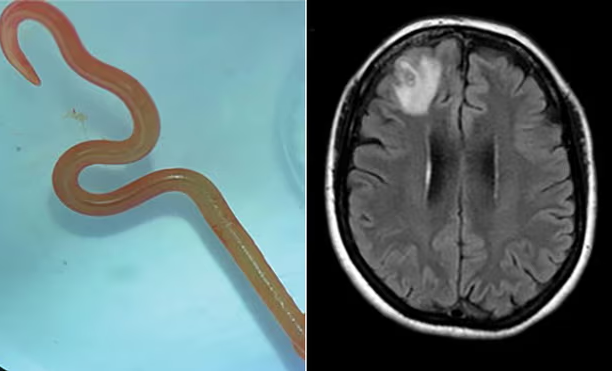

نیورو سرجن ڈاکٹر ہری پریا بندی نے اپنی مریضہ کے دماغ سے آٹھ سینٹی میٹر لمبا طفیلی (پیراسائیٹ) راؤنڈ ورم نکالا تھا اور وہ ڈاکٹر سنجے سیننائیک اور ہسپتال کے دیگر ساتھیوں سے مشورہ کرنا چاہتی تھیں۔

یہ دراصل آٹھ سینٹی لمبے اس راؤنڈ وارم تھا جسے اوفیڈاسکیریز رابرٹسی کہا جاتا ہے اور جس کے بارے میں محققین کا کہنا ہے کہ یہ کینگروز اور سانپوں کی ایک قسم پائیتھون میں پایا جاتا ہے تاہم انسانوں میں نہیں۔

متعدی امراض کے ماہر ڈاکٹر سنجے سینانائیک کا کہنا ہے کہ ’دنیا میں اوفیڈا سکیریز کی انسانی دماغ میں موجودگی کا یہ پہلا کیس ہے۔‘

خاتون کے دماغ کے سکین کے بعد اس کیڑے کی ڈی این اے ٹیسٹنگ سے شناخت ہوئی۔